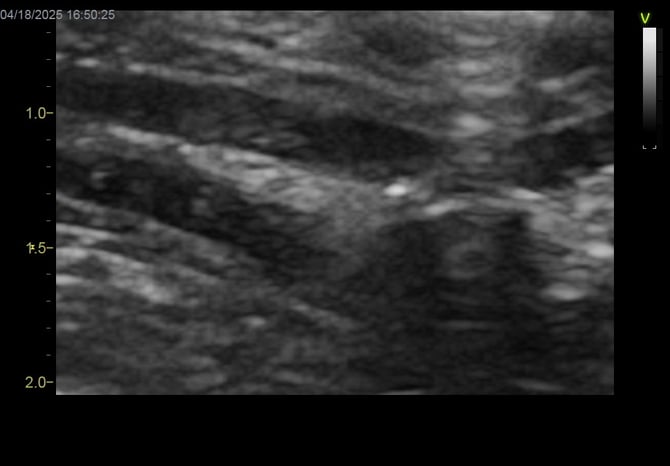

図1

初診時腹部超音波検査で、小腸粘膜に高エコー像およびリンパ管拡張所見が見られ炎症性腸疾患と仮診断し、プレドニゾロンの投与を開始した